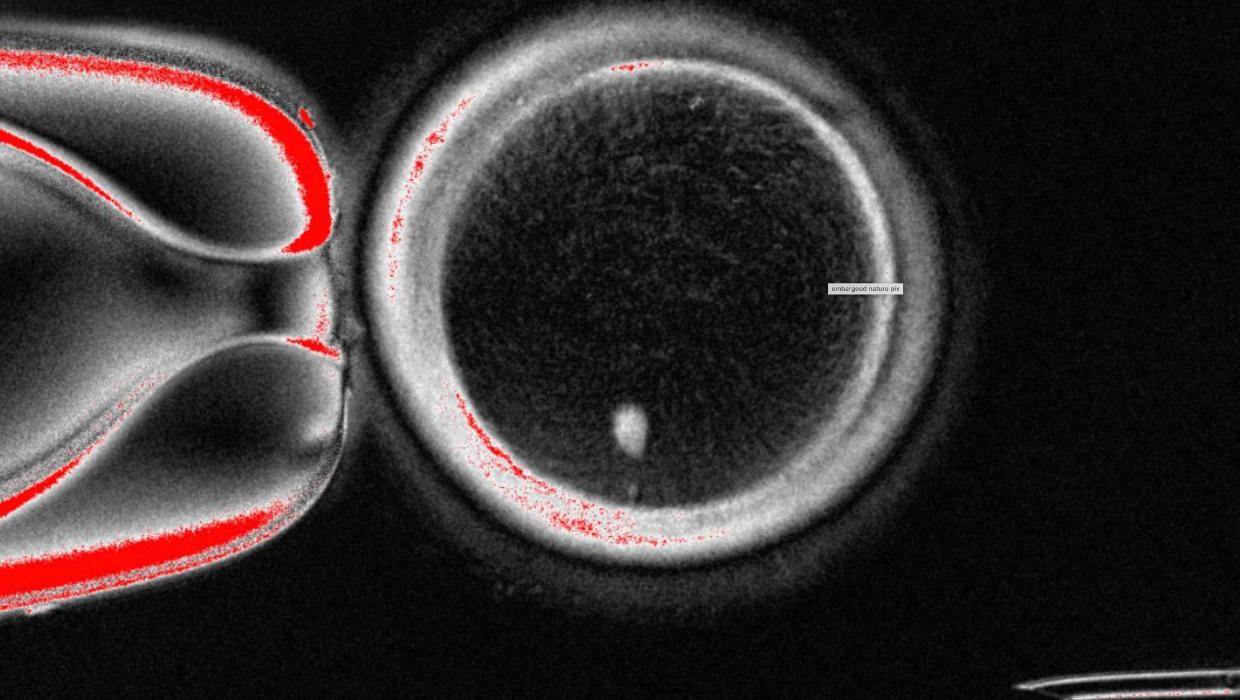

Scientists in the United States have achieved a significant breakthrough by transforming human skin cells into fertilizable eggs. This pioneering research marks a crucial step toward the development of lab-grown eggs and sperm, with the potential to assist individuals facing challenges in conception.

In a study published in October 2023, researchers detailed their innovative technique, which involves reprogramming skin cells to develop into oocyte-like cells. These cells can then undergo fertilization, raising the prospect of creating viable gametes from somatic cells. The implications of this advancement could be profound, offering new avenues for fertility treatments and potentially addressing infertility issues for numerous couples.

The study results demonstrate that the reprogrammed skin cells possess the necessary characteristics to develop into functional eggs. When these oocyte-like cells were fertilized in laboratory settings, they showed the potential to develop into early-stage embryos, indicating a significant advancement in reproductive technology.